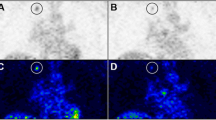

During radiotherapy, the maximum decline in T/NT measured for FDG and FLT was 42 ± 18% (scan 3) and 49 ± 16% (scan 4; mean ± SD), respectively. At all time points, FLT uptake was higher than that for FDG, but FDG uptake showed less variation. For FLT, the decrease seen in the first week was followed by a much larger decrease in the second week (Fig. 3a, b). For FDG as well as for FLT, a significant decline in retention (relative T/NT ratio) was observed at scan 2 (day 4). Next to this observation, for FLT, the most significant decline in retention (relative T/NT ratio) was observed at scan 4 (day 12), whereas for FDG, this was already noted from scan 2 (day 4). Table 3 summarizes the results from the statistical analyses correlating T/NT and changes in T/NT (ΔT/NT) to tumor volumes at baseline (V baseline) to exclude differences in the initial situation and at day 29 (V day29). For FDG, no statistical significant correlation was found between V baseline and any of the T/NT values. In contrast, for FLT, statistical significant correlations were found for both V baseline and V day29 with T/NT and ΔT/NT of scans 2 and 3. Statistical significance disappeared with respect to scan 4 possibly because of the 4-day period between the last radiotherapy and scan 4. For FDG, only a significant correlation was found between V day29 and T/NT baseline. A predictive effect of baseline tumor volume was not found.

To study response monitoring in the HNX-OE xenograft model, a protocol was designed mimicking conventional clinical radiotherapy protocols, with the view of predicting effects of radiotherapy as soon as possible. From FDG studies, it is known that, in general, changes in FDG signal appear before changes can be detected in tumor volume [34]. For FLT, however, little is known. Based on the radiosensitivity experiments, it was assumed that fractionated radiotherapy with a total dose of 22 Gy would result in an adequate radiation dose for determination of the time course of FDG and FLT signals after radiotherapy under conditions that are relevant clinically. Indeed, a significant reduction in tumor volume was observed after this treatment. Tumor growth curves in both FDG and FLT groups followed a similar pattern over time. FLT uptake was, however, higher then that of FDG, and both FDG and FLT uptake showed rapid response to radiotherapy. The decrease in FLT uptake as seen in the first week was followed by a much larger decrease in the second week, which was not the case for FDG uptake. For FDG as well as for FLT, a significant decline in retention (relative T/NT ratio) was observed at scan 2 (day 4). Next to this observation, for FLT, the most significant decline in retention (relative T/NT ratio) was observed at scan 4 (day 12); whereas for FDG, this was already noted from scan 2 (day 4). Statistical significance disappeared with respect to scan 4 possibly because of the 4-day period between the last radiotherapy and scan 4. In a study of Sugiyama et al. [35], C3H/He mice, bearing SCCVII tumors (murine SCC), who received a single dose of 20 Gy, showed a rapid response to radiotherapy both with respect to FDG and FLT uptake in line with the present results.